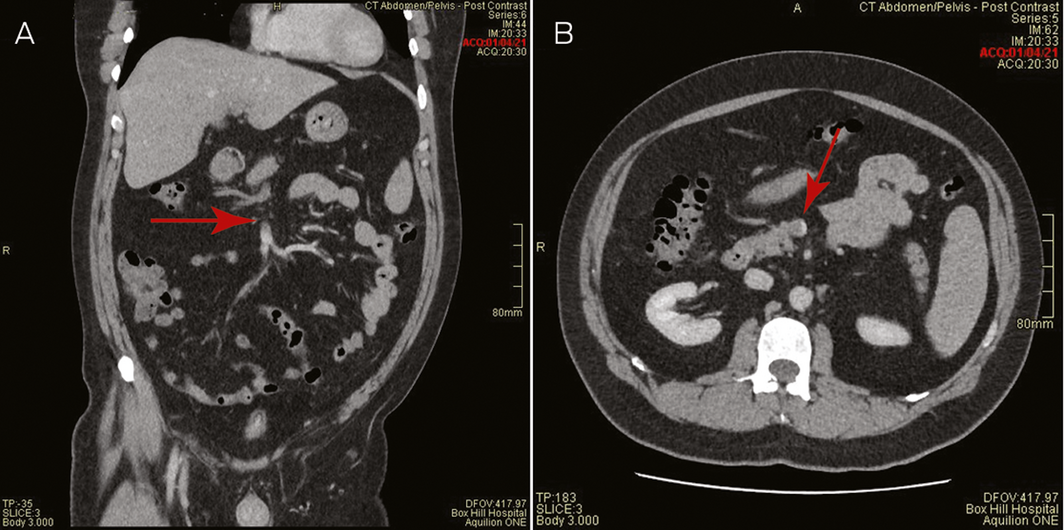

A 44‐year‐old male health care worker presented with fevers, fatigue and head “fogginess” with abdominal discomfort and increased bowel frequency 8 days after receiving his first dose of the COVID‐19 vaccine (ChAdOx1‐S [recombinant]) (AstraZeneca). He was previously well, with a past history of depression and was only taking escitalopram. He had no prior thrombosis or exposure to heparin. The low platelet count, 70 × 109/L (reference range, 150–400 × 109/L), and markedly elevated D‐dimer, 114 mg/L (upper limit of normal, 0.5 mg/L), with vague abdominal pains prompted a computed tomography (CT) venogram of the abdomen, which demonstrated thrombosis with complete occlusion of the portal and splenic veins and protrusion of a tongue of thrombus into the superior mesenteric vein (Box 1). CT venogram of the head did not show central venous sinus thrombosis.